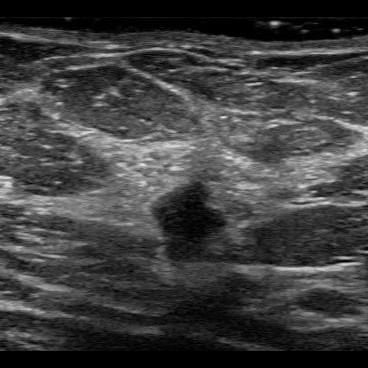

Deep learning has achieved promising results assessing different types of medical images [1]. However, for safe deployment and trustworthiness, the algorithms have to be able to tell when they cannot make proper assessments. This includes detecting out-of-distribution (OOD) data, which comprise data samples that the algorithm has not learned how to interpret. A lot of progress has been made in this area in recent years with numerous methods having been suggested for OOD detection [2] and uncertainty quantification [3]. In this study we explore different methods for OOD detection, including uncertainty-based ones, with the aim of being used in a tool for breast cancer classification in point-of-care ultrasound (POCUS) images. Breast cancer is the most common type of cancer amongst women worldwide [4]. Detecting breast cancer in an early stage improves patient outcome both in terms of mortality and morbidity, but access to diagnostics is lacking in many low- and middle-income countries [5, 6]. A possible solution could be a deep learning-based algorithm analyzing images captured with a POCUS device and using a smart-phone for visualization. Examples of POCUS images capturing breast tissue are shown in Fig. 1. In a previous study it has been shown that a convolutional neural network (CNN) can classify breast cancer in POCUS images with good performance [7]. Here we extend this work by exploring and evaluating three different OOD detection methods: softmax, energy score and deep ensembles. This should enable detecting unsuitable images during inference, which is crucial to make reliable assessments in a real world setting.

The ID data consists of POCUS images capturing breast tissue collected with a GE Vscan air probe [13] at Skåne University Hospital, Malmö. This data set contains images of normal tissue as well as benign and malignant lesions, see Fig. 1. The data was split into training and test set. In addition to the POCUS training set, a conventional ultrasound (US) data set of breast tissue was also used for training. These images were collected with Logiq E9 and Logiq E10 ultrasound machines at Skåne university hospital, Malmö. The sizes of the ID data sets are shown in Table 1.